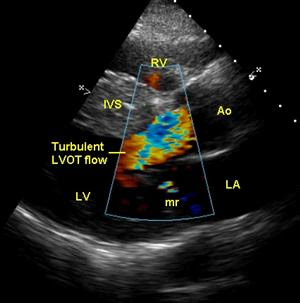

Recordar é preciso: Convidados - Gradiente na via de saída do VE

Diagnóstico diferencial para Gradiente na Câmara de Saída do Ventrículo Esquerdo:

- Miocardiopatia Hipertrófica Obstructiva

- Cardiopatia Hipertensiva

- Feocromocitoma

- Enfarte Agudo do Miocárdio

- Hipovolémia

- Inotrópicos

Enviada p Ana Feijão.